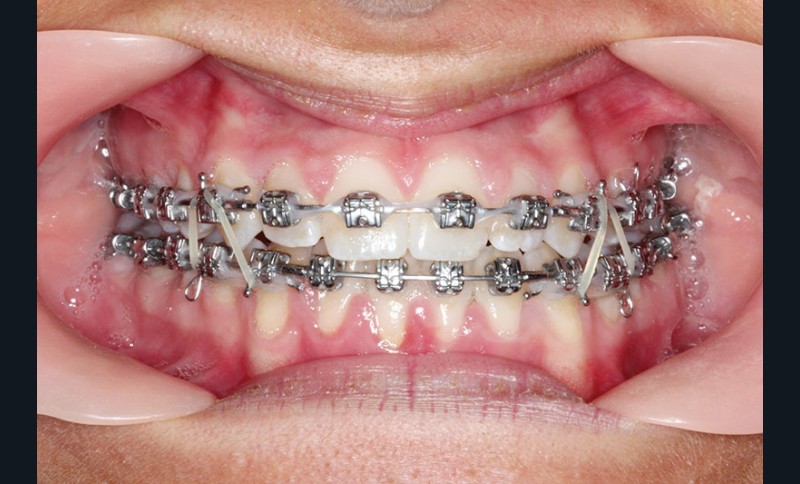

2e phase : mise en place du système multibague Carriere SLX (fig. 7 à 9)

Nous continuons le port des élastiques…